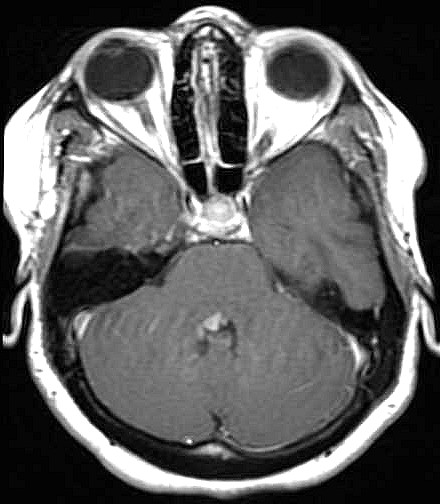

| Fem. 17a. |

| Nódulo sólido homogêneo preenchendo o III ventrículo, com limites precisos, com hipossinal em T1 e hipersinal em T2 e FLAIR, que se impregna por contraste paramagnético. Lesão menor implantada no assoalho do IV ventrículo provavelmente representa disseminação por via liquórica. |

| CORTES AXIAIS, T1 COM CONTRASTE | ||

| F. 17a. Tumor teratóide rabdóide atípico de III ventrículo. RM | HE | VIM, GFAP | HHF35, desmina, 1A4 | AE1AE3, EMA |